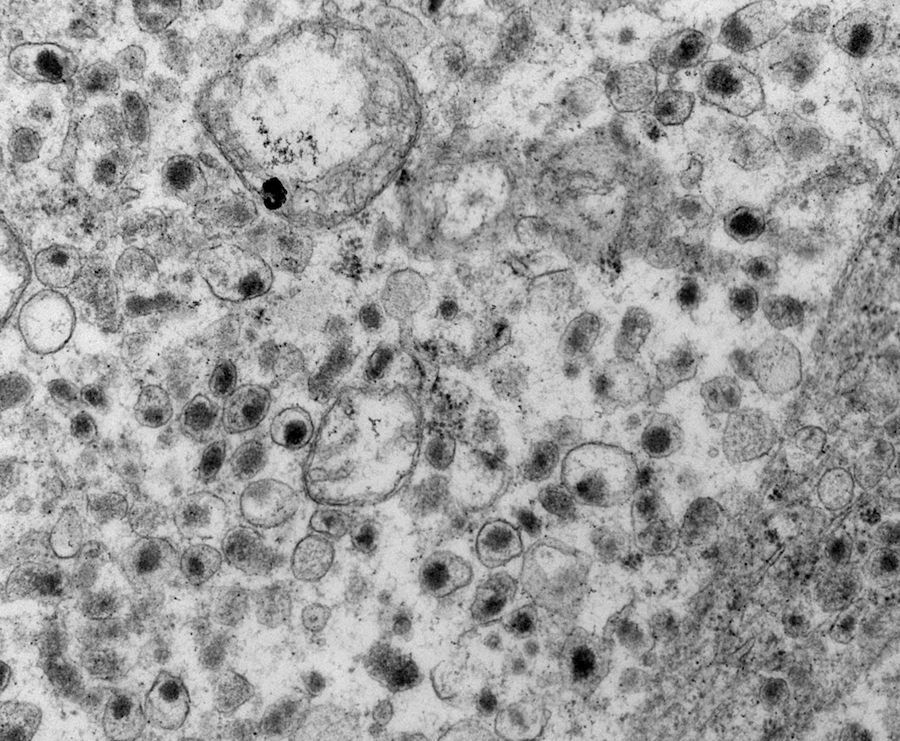

Electron microscopy description

- Chief cells are polygonal with well developed rough endoplasmic reticulum, prominent Golgi complex and abundant cytoplasmic neurosecretory granules (Arch Pathol Lab Med 1980;104:46)

- May have giant mitochondria with paracrystalline inclusions

- Sustentacular cells wrap around chief cells and lack neurosecretory granules

- No desmosomes

Electron microscopy images